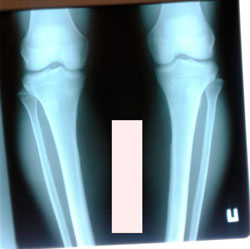

перед крутками

image-17-10-20-09-57-2.jpg